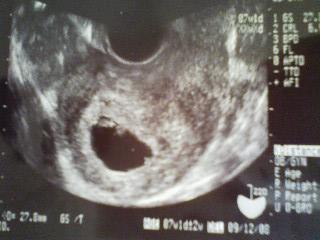

まだ8週目のところ、土曜日にトイレに行ったら少し出血がありましたとりあえずおなかも痛くないし、痛みがなければ大人しくしてれば大丈夫かなとそのまま大人しくしてたら日曜日の雪こんなに積もったのは初めてなのでシュン君を連れ出して雪を歩く感触を楽しみましたとにかく転ばないようにだけは気をつけて行きましたよいつもは髪の毛が少ないからかゆいのか嫌がる帽子も寒いのには負けたらしく、ちゃんとかぶってくれましたそんな事をしつつの日曜日、家に帰ってからはまた大人しく過ごしておりました出血は土曜日の一度だけだったのでこのまま様子を見てもいいかなと感じてたんですが月曜朝一番のトイレでまたしても出血これはもう病院に行って確かめないと恐いということで行ってきました妊婦検診は通常、予約してあるはずなので待たなくても済むのですが今回は急の事だったのでシュン君を連れての待ち時間1時間半ほど最初は目新しいオモチャに気をとられていたのですが最後の方は受け付け前でグルグル回転したり、カルテの戸棚開けたり他の患者さんの服の模様を触りに行ったり、患者さんと患者さんの間に座ってベタベタしたりこれはもう外で待つしかないと思った瞬間呼ばれたのですが診察台に座った私に興味津々『なに?!なにやってるの?!』とばかりにカーテンの仕切りを行ったり来たりそれでも赤ちゃんは無事大きくなってて一安心出血は前回胎盤に見えてた血管のぷつぷつが出血したということでしたそんなわけで、今回の胎盤は前回と比べてきれいなものちょっと手や足らしいものも見えてきました診察台から降りて、先生と話し始めたところその間にシュン君、何と!診察台に乗ってました看護婦さんに降ろされたものの先生には「今までお子さんがいろいろ居たけど、診察台に乗ったのは初めて!」と笑われてしまいましたでも無事に赤ちゃんを確認出来て本当、良かったです

25日に二歳になったシュン君、土曜日にお誕生日会を開きました。ただし、その前にようやく産婦人科へ・・・ちゃんと妊娠してました~ちょうど七週目、出産予定日は9月13日です。胎嚢もしっかり見えて、心臓もちっちゃく動いてましたお誕生日会では旦那さんの両親、お祖母ちゃんが各々二人来てくれたのですが安定期に入るか、太ってばれるまでは黙っておくことにしました前日作ったバースデーケーキはイチゴたっぷりのショートケーキですろうそくを消すのが面白かったらしく、もっとやりたいとばかりにせがんだシュンくんでしたがカットされてきたケーキで正気を取り戻してしっかり1カット分ちゃんと完食してました